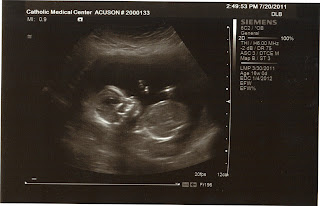

Wednesday, July 20, 2011

Today I had my 4 month follow up appointment. We had this ultrasound done, this is the 3rd time but figured I would just post this one since there are so many! Kind of looks like the baby is waving! Still no definitive answer but the doctor is still leaning towards a girl. It's still a bit early to tell so we are waiting before we get rid of all our old boy stuff!

I have been on a no lifting restriction for the past 10 days but the doctor said next week I can go back to normal activity. All is well and I'm feeling great. I've gained a total of about 5 pounds but it certainly looks a lot more than that! No cravings yet but still not back to wanting vegetables as much as I should although I eat fruit all day long.

I have a follow up appointment in 2 weeks and hope to get a belly picture up before then so you can see how I'm growing.